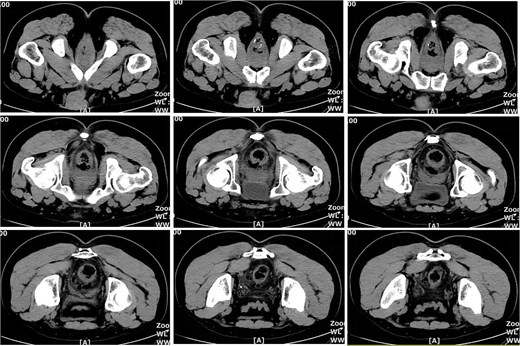

On postoperative Day 21, a follow-up pelvic CT scan indicated local gas accumulation around the rectum, suggesting an absorption phase of the infection (Fig. 4). By postoperative Day 28, a pelvic CT scan demonstrated minor gas accumulation at the anterior edge of the rectosigmoid junction, consistent with infection resolution and gas absorption in the surrounding area (Fig. 5). By postoperative Day 49, a pelvic CT scan revealed no abnormal density shadows in the perianal skin and soft tissues, with preserved fat planes (Fig. 6), indicating complete resolution of the perirectal infection and restoration of normal clinical status.